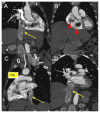

Uterine intravenous leiomyomatosis is an uncommon tumor, usually arising from the uterus, with nodular masses which extend intravascularly over variable distances and may reach the inferior vena cava, right atrium, and pulmonary arteries. Early diagnosis and surgical intervention are crucial as intracardiac leiomyomatosis not only causes cardiac symptoms but may result in pulmonary embolism and sudden death. Complete tumor resection is key in disease management, thus rendering cardiac-extending uterine intravenous leiomyomatosis one of the most challenging conditions for surgical treatment. The use of interventional radiology procedures can facilitate the surgical approach. We report the case of a massive pelvic recurrence of uterine leiomyomatosis with intracardiac extension and pulmonary embolism, analyzing management and surgical outcomes, highlighting the role of interventional radiology during the therapeutic pathway. Nonetheless, there are currently very few data available concerning the use of interventional radiology procedures in the therapeutic strategy of uterine intravenous leiomyomatosis with intracardiac extension.